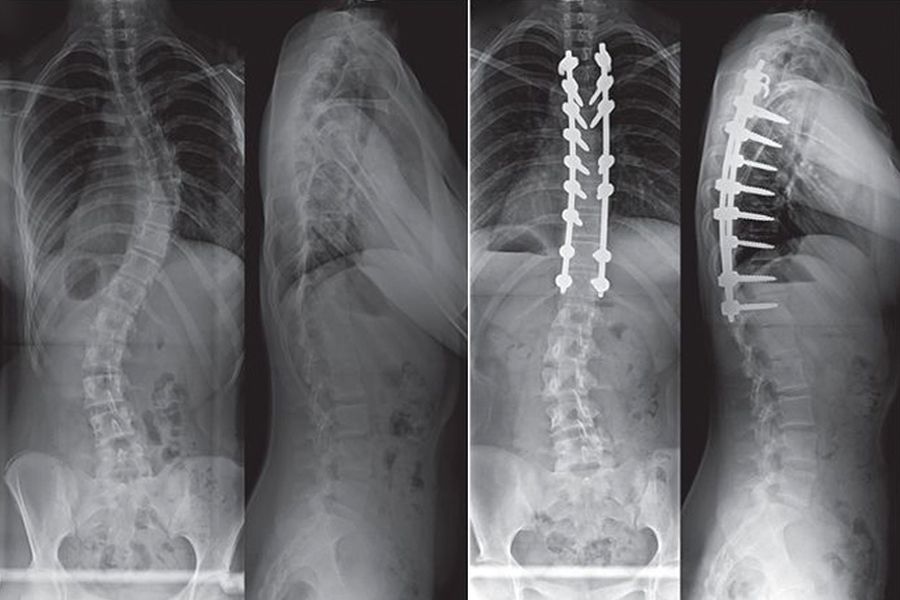

Tıbbi görüntüleme: Eklem ve omurga problemlerinin tedavi öncesi ve sonrası röntgen karşılaştırması

Avrupa Rejeneratif Tıp Enstitüsü'nde, yaşları 40 ile 85 arasında değişen, ileri derecede eklem hasarı olan 2450 hasta üzerinde yapılan OZPHYZEN klinik çalışmasının sonuçları tıp dünyasında şok etkisi yarattı: